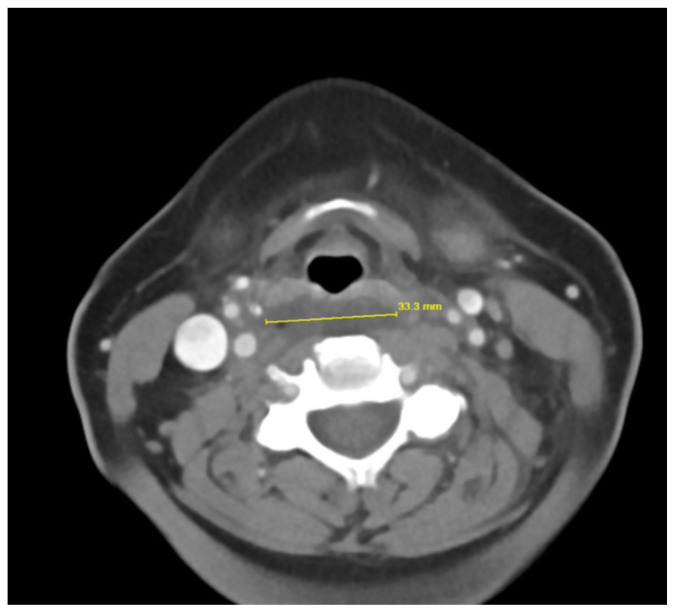

Retropharyngeal abscess (RPA) is an uncommon yet potentially life-threatening condition that is more often seen in young children and may be misdiagnosed in adults presenting with atypical features.1 Retropharyngeal abscess results from spread of antecedent upper respiratory tract infection or traumatic inoculation via foreign body ingestion or medical instrumentation. Clinically, RPA may present with fever, pharyngitis, neck pain, and dysphagia. Diagnosis is often confirmed with imaging studies. We present a case of a 66-year-old female with asthma, hypertension, and gastroesophageal reflux disease (GERD) who presented to the emergency department (ED) for evaluation of neck fullness, shoulder pain, dysphagia, and abdominal pain starting less than 24 hours prior to presentation. Computed tomography (CT) revealed a prevertebral/retropharyngeal fluid collection from the odontoid tip to the C4 vertebral body measuring 5.4 × 1.0 × 3.3 centimeters (cm) in size with associated edema at the left neck base extending into the upper chest, suggestive of retropharyngeal abscess. The patient received intravenous (IV) vancomycin and piperacillin/tazobactam and was transferred to a higher level of care for otolaryngologist evaluation. The patient remained stable without airway compromise while in our department. This case underscores challenges in diagnosing atypical presentations of RPA in adults, emphasizing timely recognition to prevent complications.